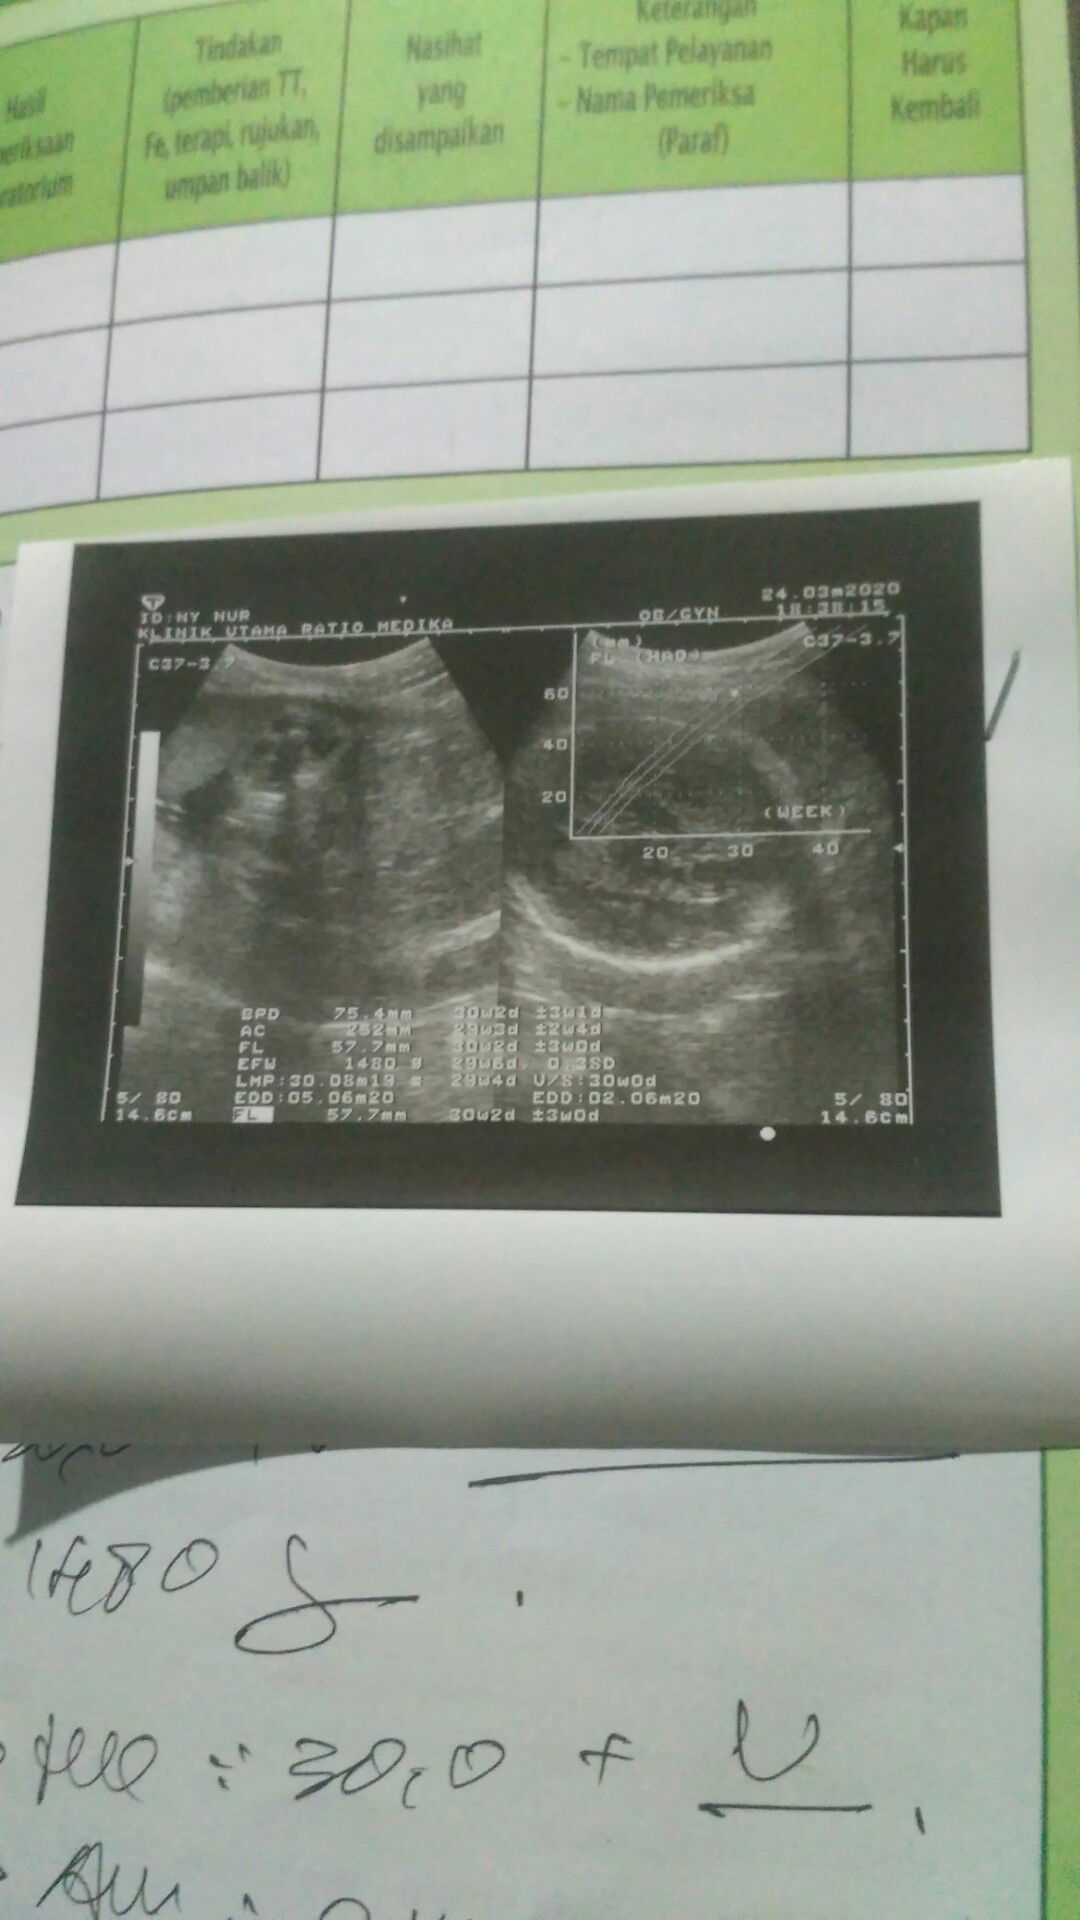

Bun maaf mau tanya.. Itu panjang bayinya yg mana ya. Apakah berat 1480 normal utk kehamilan 30week dengan bbj 1480